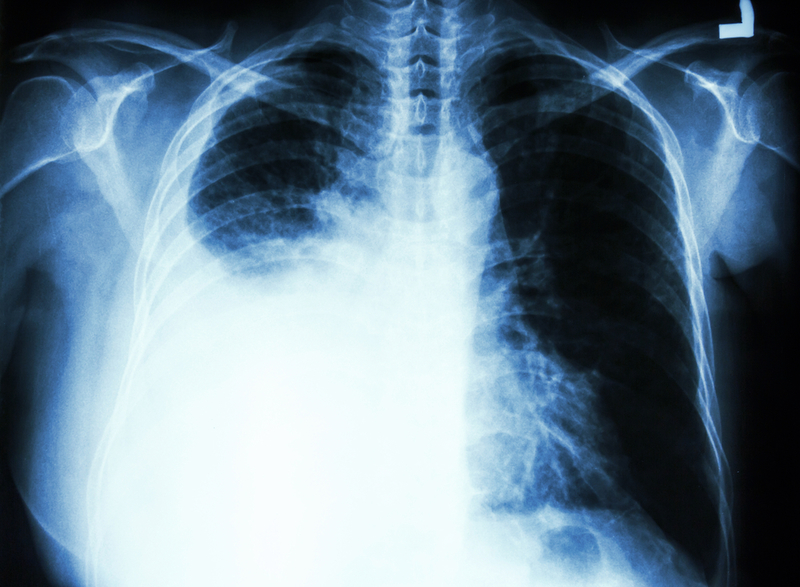

A new guideline to help clinicians manage malignant pleural effusions (MPEs) has been developed by the American Thoracic Society, the Society of Thoracic Surgeons, and the Society of Thoracic Radiology. The clinical practice guideline is published online in the October 1 American Journal of Respiratory and Critical Care Medicine.

MPEs account for 125,000 US hospital admissions each year that are estimated to cost $5 billion. Patients diagnosed with a MPE live on average for 4 to 7 months.

Given this short survival period, and the fact that the majority of patients with MPE have significant dyspnea, the 14-member international panel of experts that produced the guideline said that an emphasis should be placed on patient-centered outcomes, such as relieving dyspnea in a minimally invasive manner and reducing, if not eliminating, the need for repeated procedures and health-care visits.